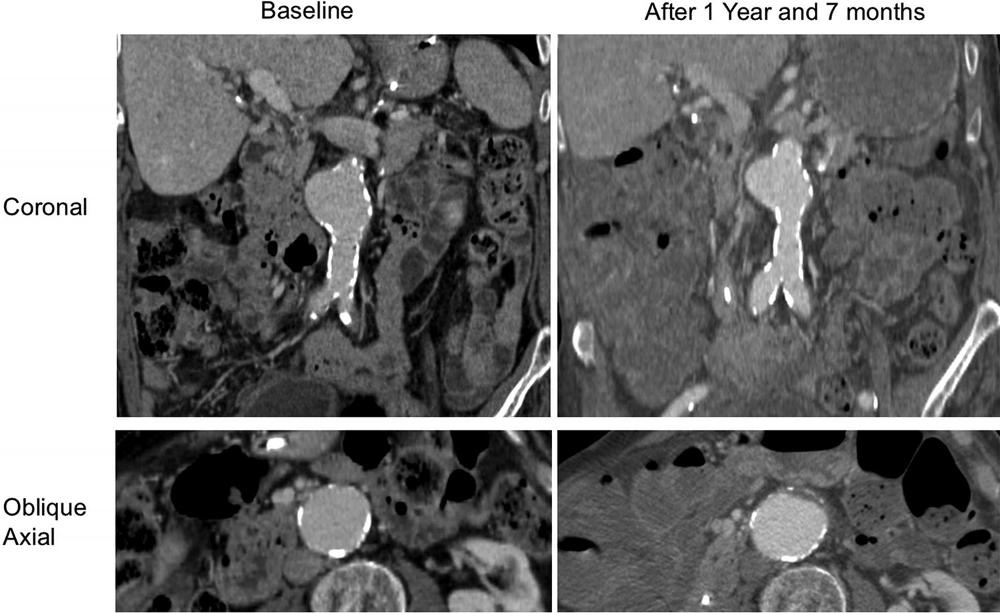

Figure 5. A patient (aged 88 years, male) with a slow-growing abdominal aortic aneurysm without intraluminal thrombus at baseline. Coronal and oblique axial contrast-enhanced CT images show that the aneurysm grew from 4.2 to 4.3 cm within 1 year and 7 months at a growth rate of 0.6 mm/y.

High-res (TIF) version